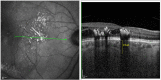

Purpose: This work aimed to longitudinally assess the peripapillary (PPCT) and subfoveal (SFCT) choroidal thickness (CT), in patients diagnosed with central (CRVO) or branch retinal vein occlusions (BRVO), correlating SFCT with central macular thickness (CMT) and PPCT with peripapillary retinal nerve fiber layer thickness (pRNFL).

Patients and methods: This was a retrospective longitudinal study of 71 eyes from 71 patients with treatment-naïve retinal vein occlusion (24 CRVO and 40 BRVO). Spectral-domain optical coherence tomography (SD-OCT, Spectralis HRA-OCT, Heidelberg) was used to measure PPCT, SFCT, pRNFL and CMT of the affected and fellow eyes at baseline (acute phase) and at 3 and 9 months post anti-VEGF treatment. IBM SPSS Statistics version 27.0 (IBM Corp., Armonk, NY, USA) was used for statistical analysis. A p-value ≤0.05 was considered statistically significant.

Results: Affected eyes presented a thicker baseline PPCT and SFCT compared to their fellow eyes both in CRVO and BRVO (p < 0.05). Both groups presented a significant decrease of PPCT in the affected eyes at 3 months compared to baseline (p < 0.05). At 9 months, compared to 3 months, PPCT remained stable (p > 0.05). Similarly, affected eyes' SFCT significantly decreased at 3 months (p < 0.05) in both groups. At 9 months, compared to 3 months, SFCT decreased in the CRVO patients (p = 0.047) but remained stable in the BRVO patients (p = 0.850). No correIations between SFCT and CMT were seen at any timepoint in both groups (p > 0.05). PPCT correlates with pRNFL in CRVO at 3 months, although no other correlations were found during the follow-up. In BRVO, PPCT did not show any significant correlation with pRNFL.

Conclusion: Both in CRVO and BRVO eyes, PPCT and SFCT at diagnosis are significantly thicker compared to the fellow eye, suggesting a possible increase in CT immediately after the occlusion, which is followed by a decrease at an early follow-up stage.